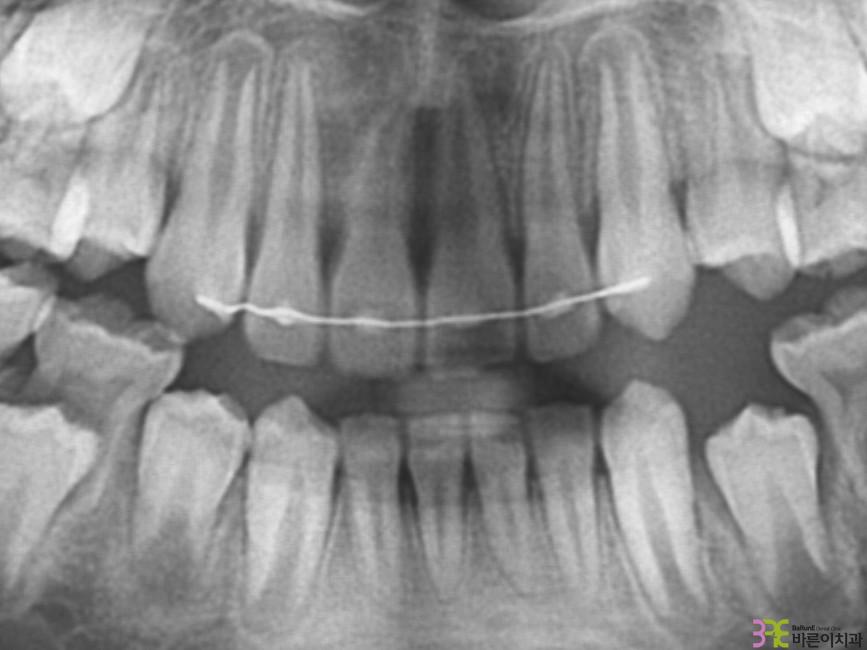

치료명

매복치 교정

치료기간

8개월

Before

After